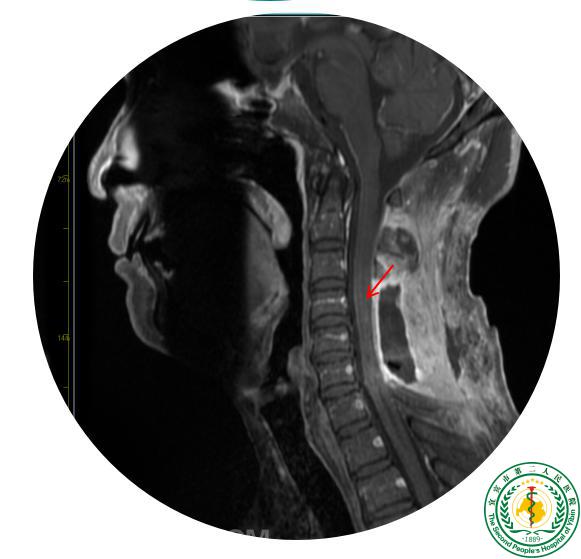

颈子肩膀又麻又痛,竟是颈椎里长了肿瘤?!

颈子肩膀又麻又痛,竟是颈椎里长了肿瘤?!39714